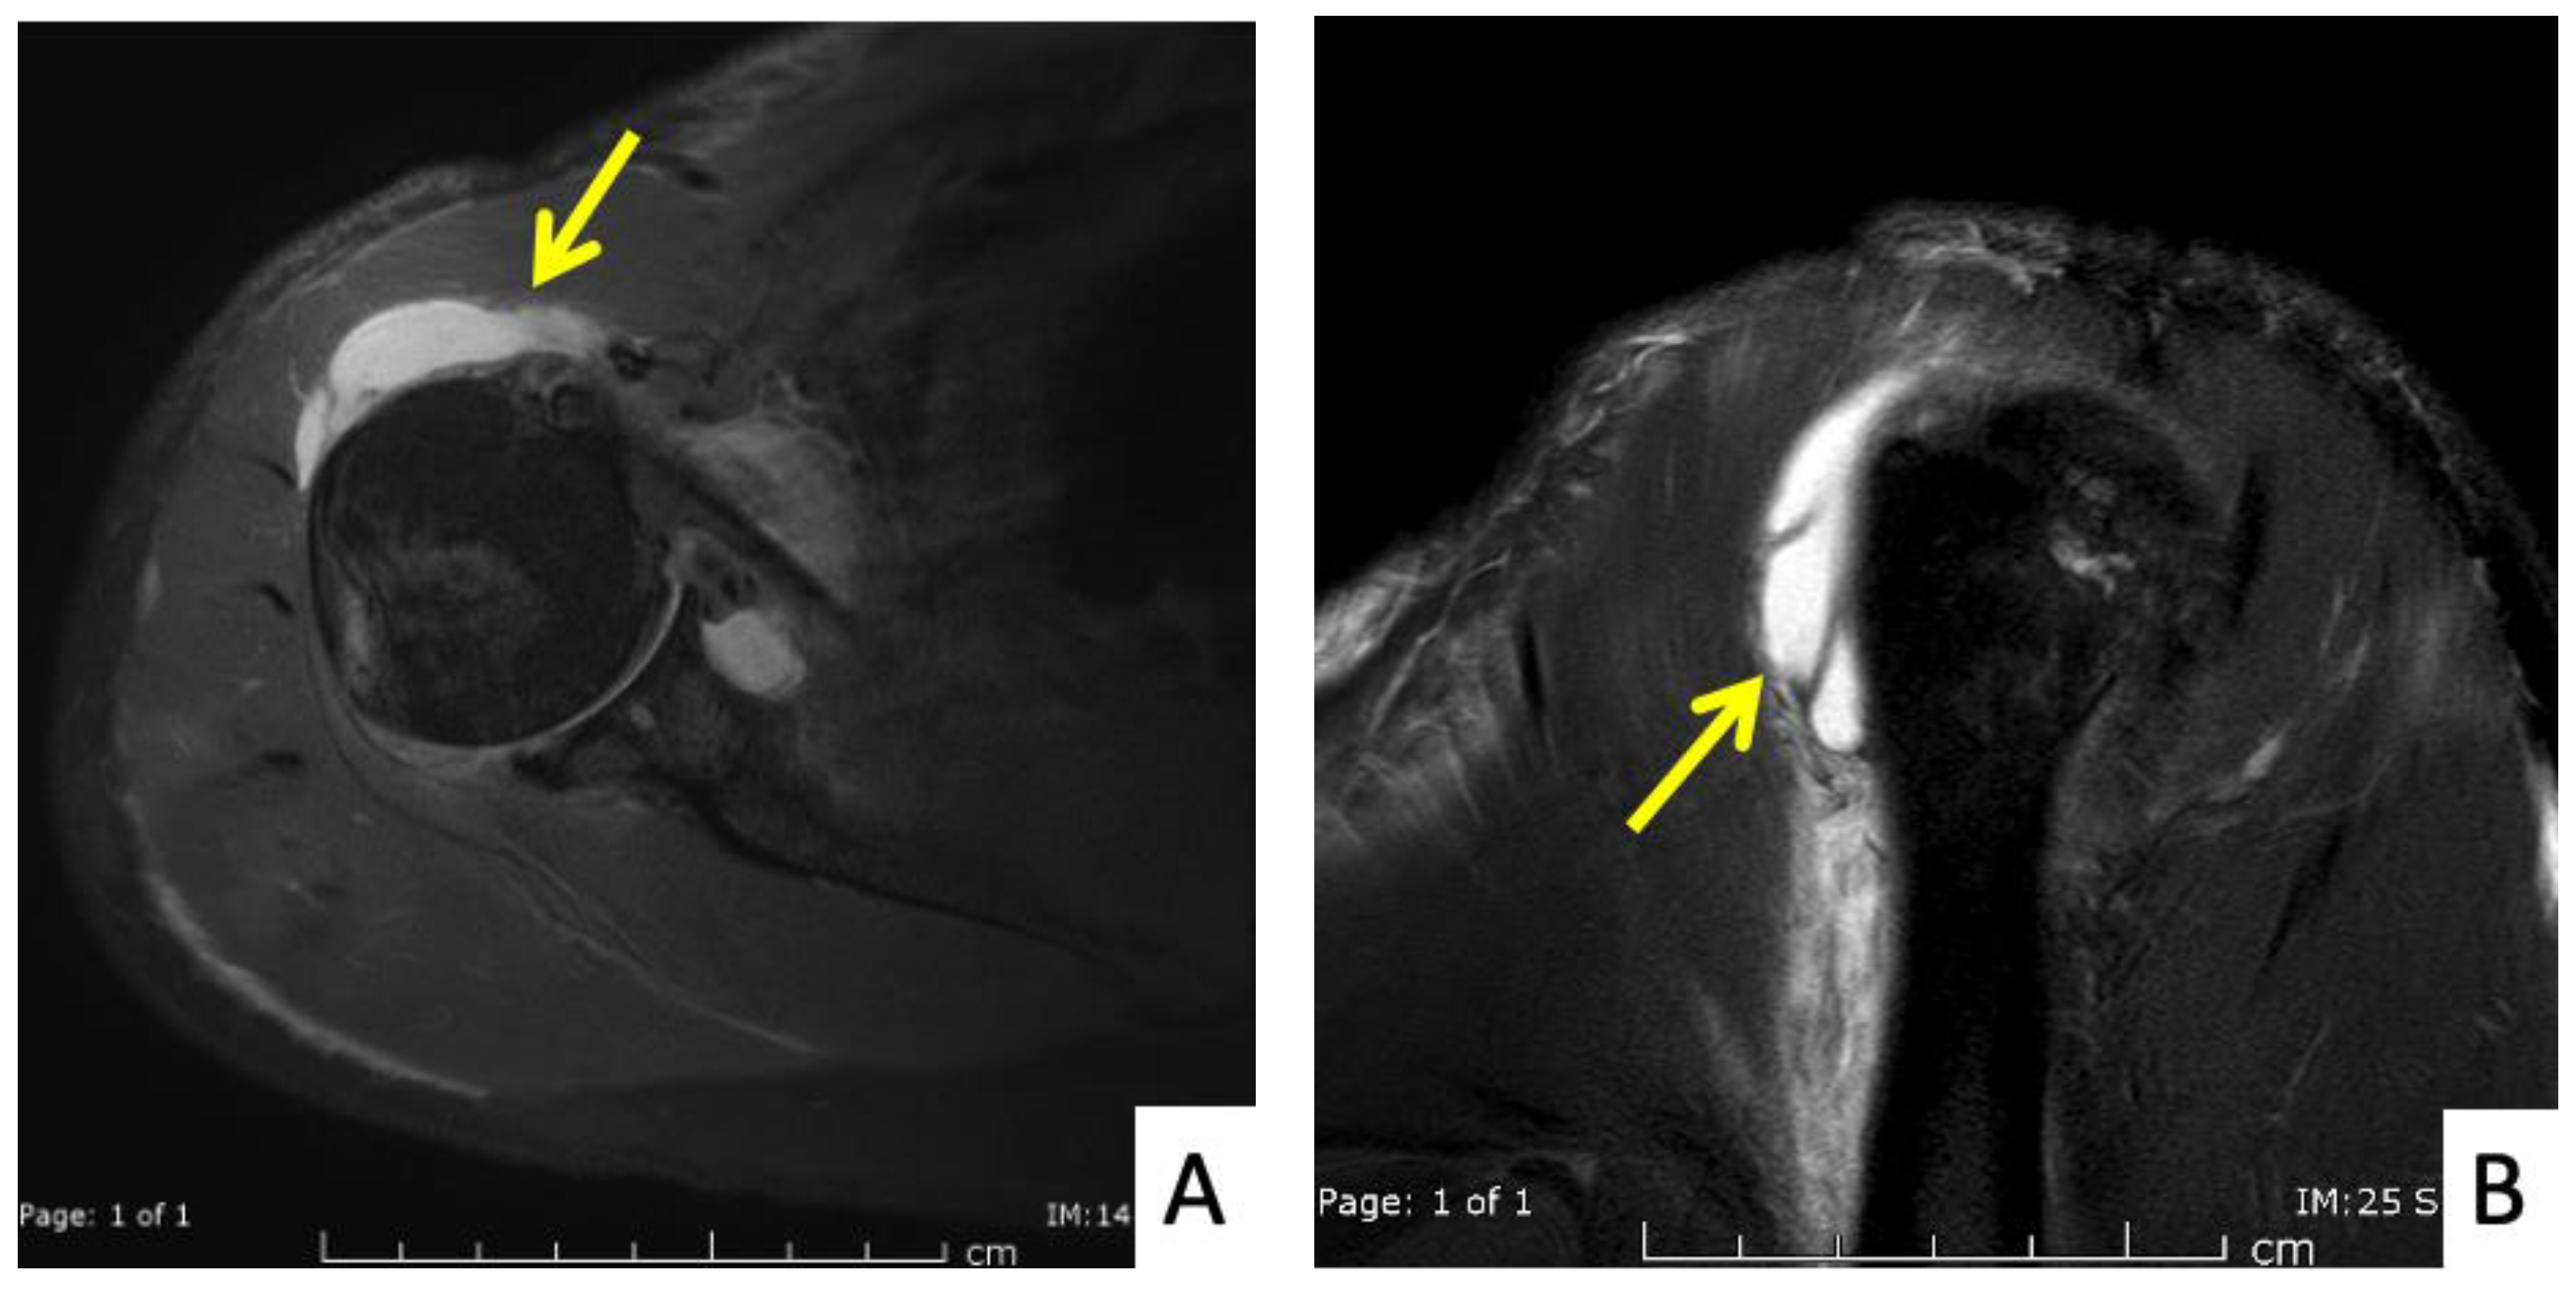

The seventh case was a 64-year-old Thai female who presented with right shoulder pain 9 weeks after a first dose of the AstraZeneca vaccine. The symptoms had begun immediately after the vaccination and gradually gotten worse, to the point that it was painful to complete daily activities and she could not sleep on her right side. In her case, the injection landmark was 1 fingerbreadth below the mid-lateral edge of the acromial process. At the OPD, the physical examination showed limited range of right shoulder motion and pain on the forward motion elevation resistance test and external rotation. Ultrasonography showed calcific tendinopathy of the supraspinatous tendon without bursitis (Figure 8A,B). She was given oral prednisolone (30 mg/day) for 5 days, and she had completely recovered at 1 month.

Figure 8.

Ultrasonographic images of the right shoulder of Patient 7. (A) A sagittal ultrasonographic image over the lesser tuberosity of the right shoulder with the patient in the external rotation position showing a few small calcific deposits (yellow arrows) within the inferior fiber of the subscapularis tendon. (B) A transverse ultrasonographic image of the supraspinatous tendon with the modified Crass position of the right shoulder showing a few small calcific deposits (white arrows) within the mid fiber.